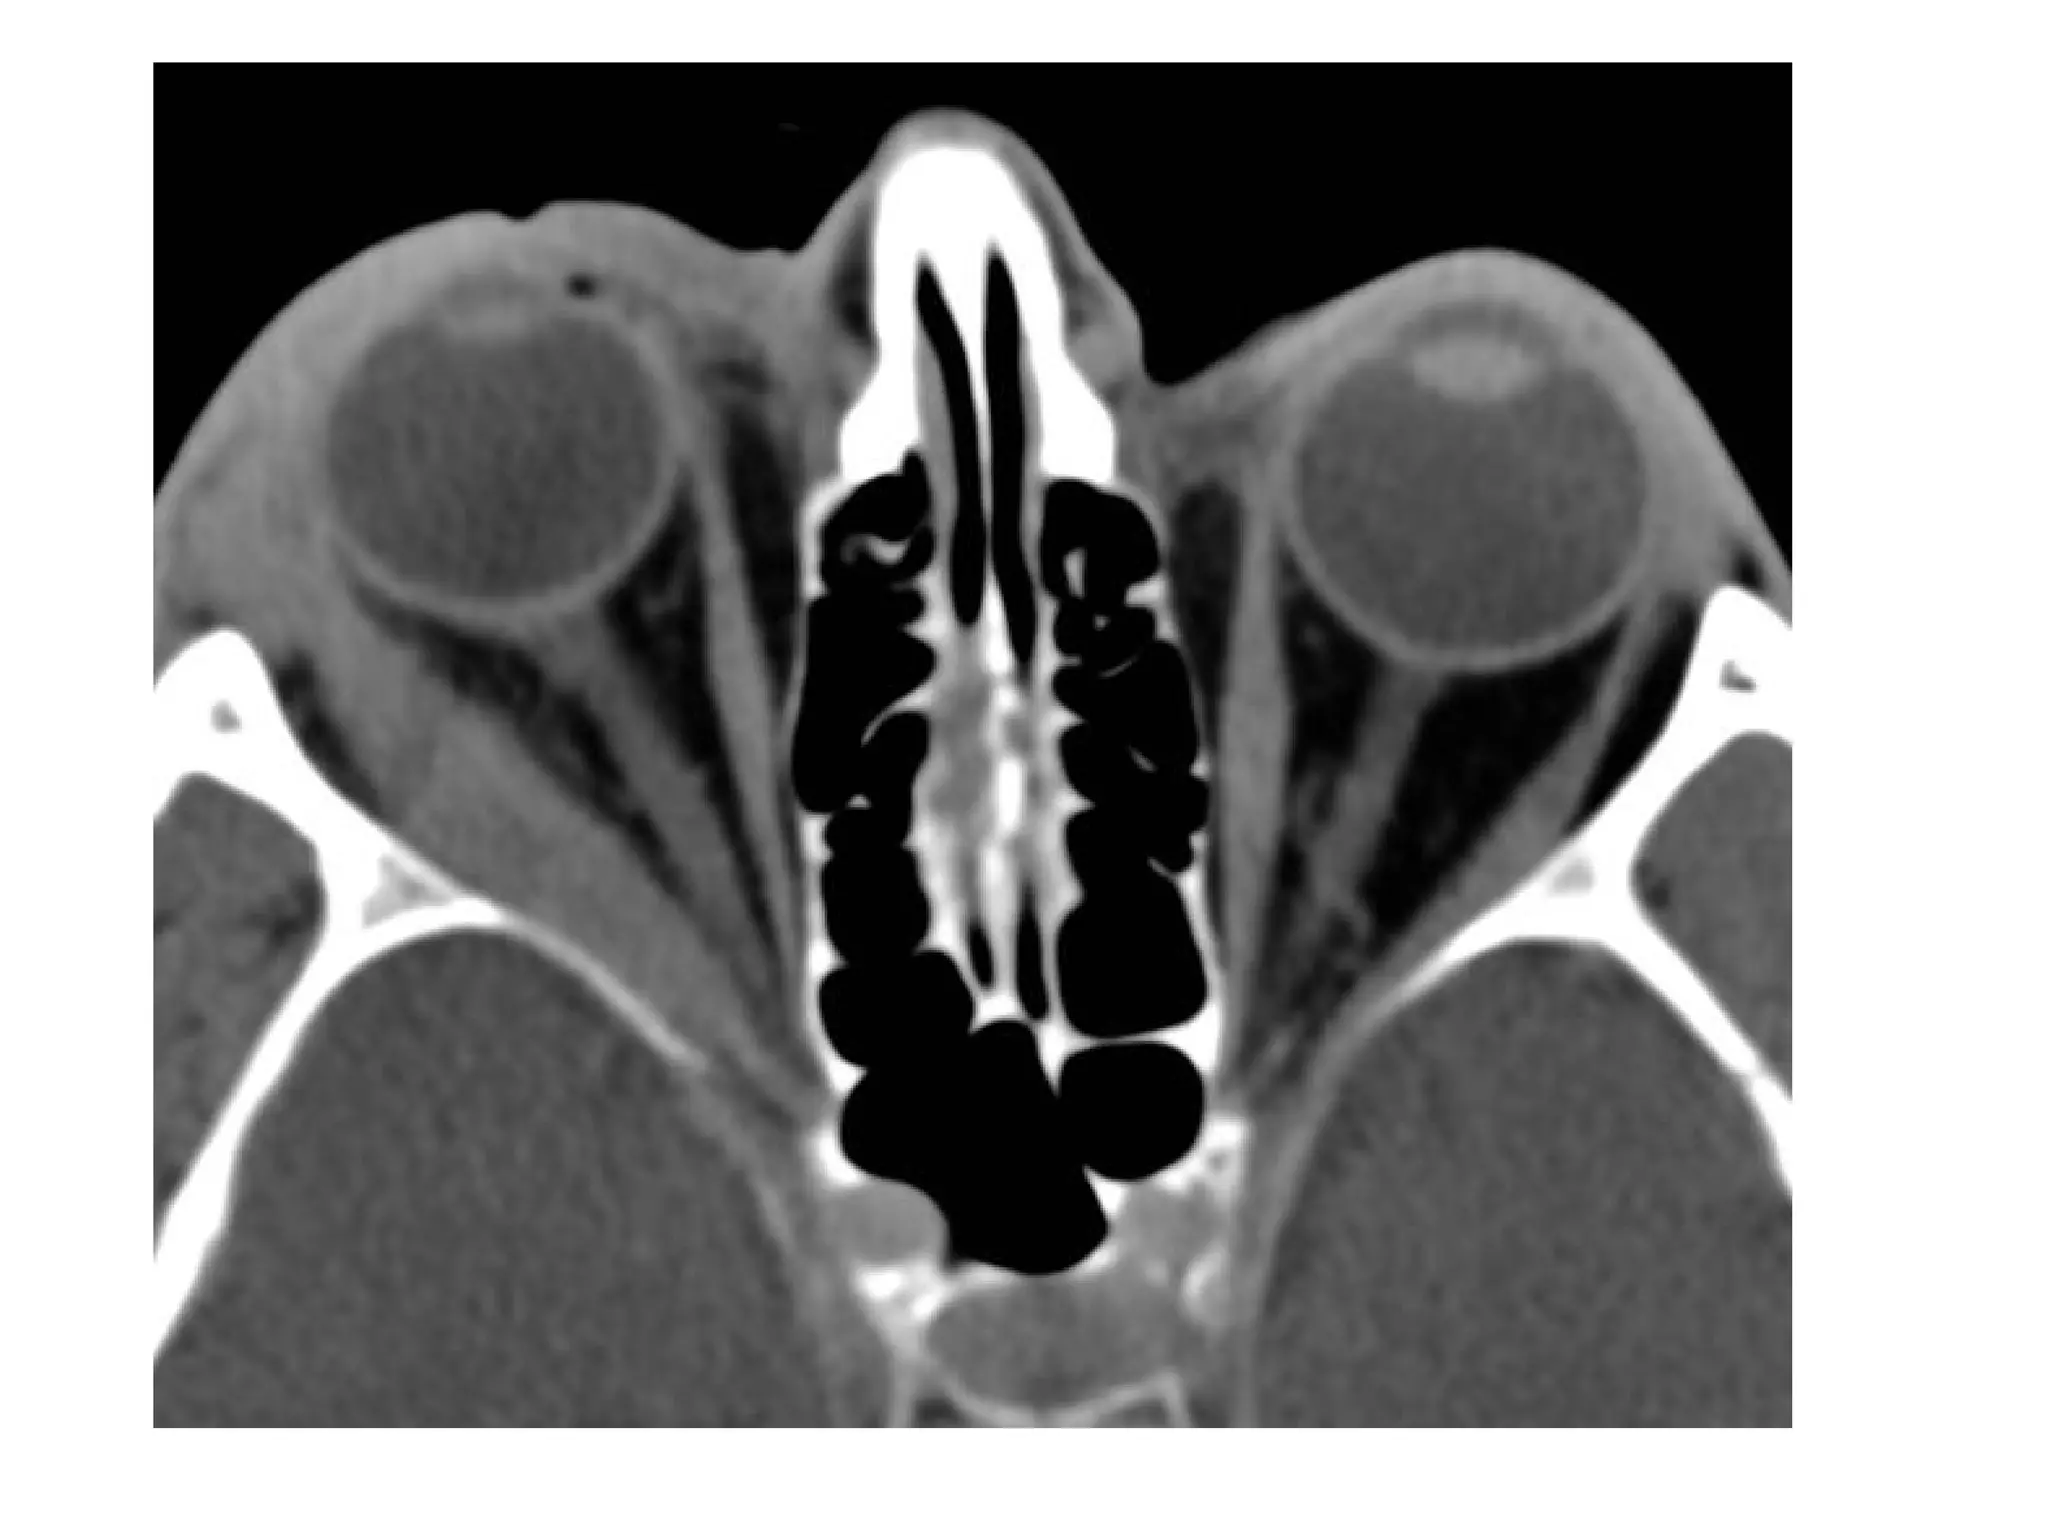

Unenhanced axial CT scan of a healthy 32-year-old man. AC = anterior

chamber, L = lens, ON= optic nerve, PS = posterior segment (vitreous

humor)